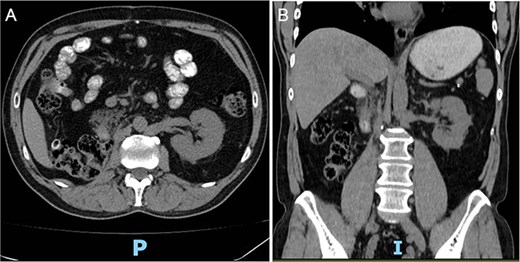

Postoperative abdominopelvic tomography (6 months later) showed post-surgical changes consistent with right radical nephrectomy and resolution of the hematoma with no evidence of recurrence (Fig. 4A–B).

(A, B) Postoperative abdominopelvic tomography (6 months later) showing post-surgical changes consistent with right radical nephrectomy and resolution of the hematoma.